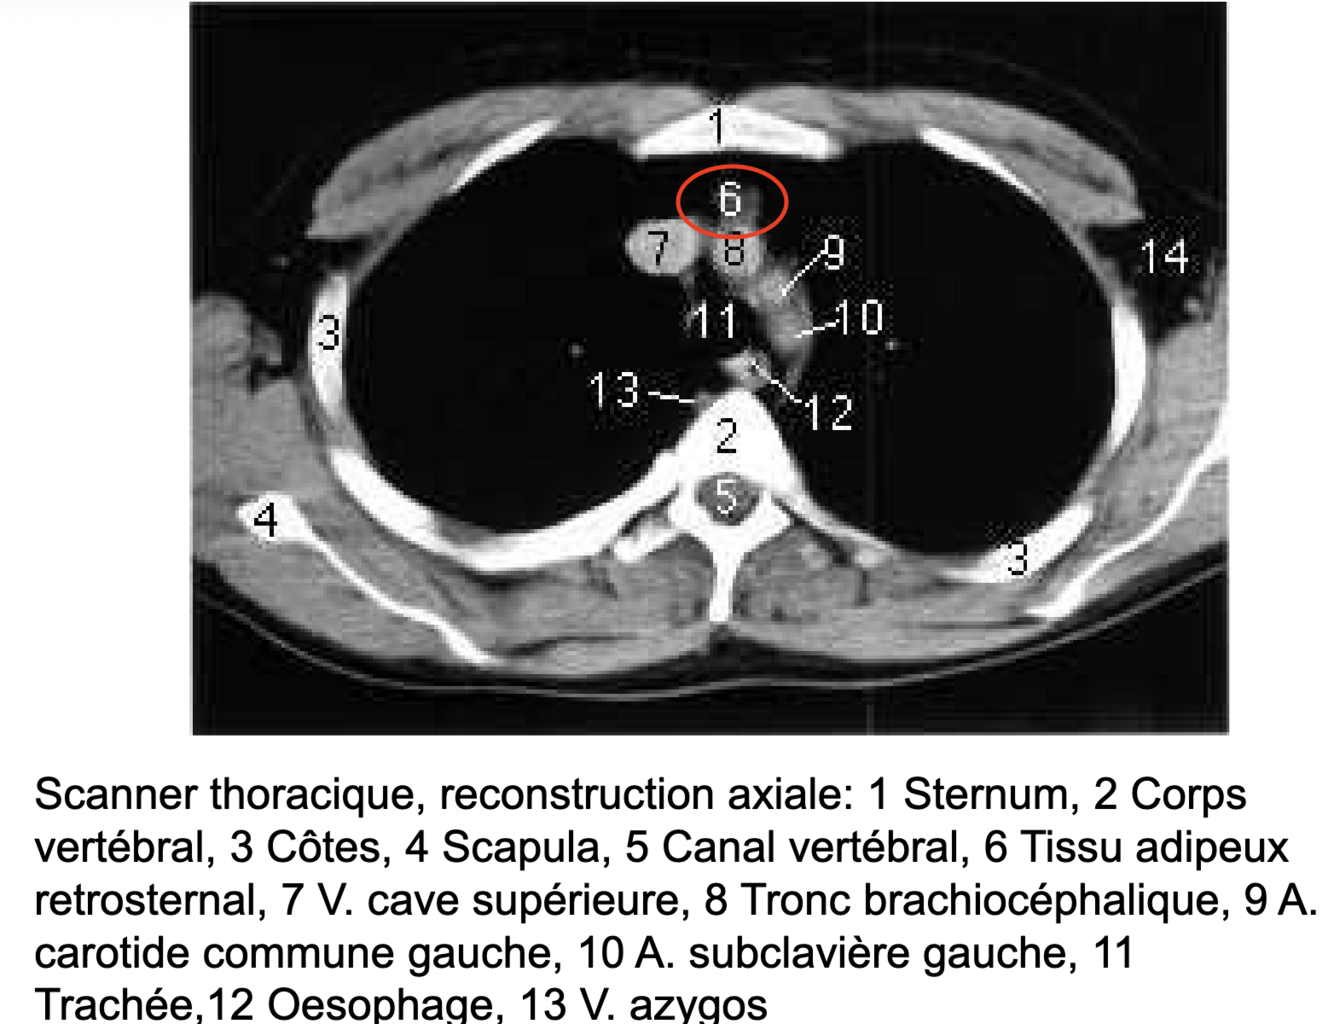

Où se situe le tissus adipeux rétro-sternal?

Il se situe derrière le sternum (= rétrosternal) mais devant le gerbe aortique (~pré-péricarde)

==> repose sur le péricarde